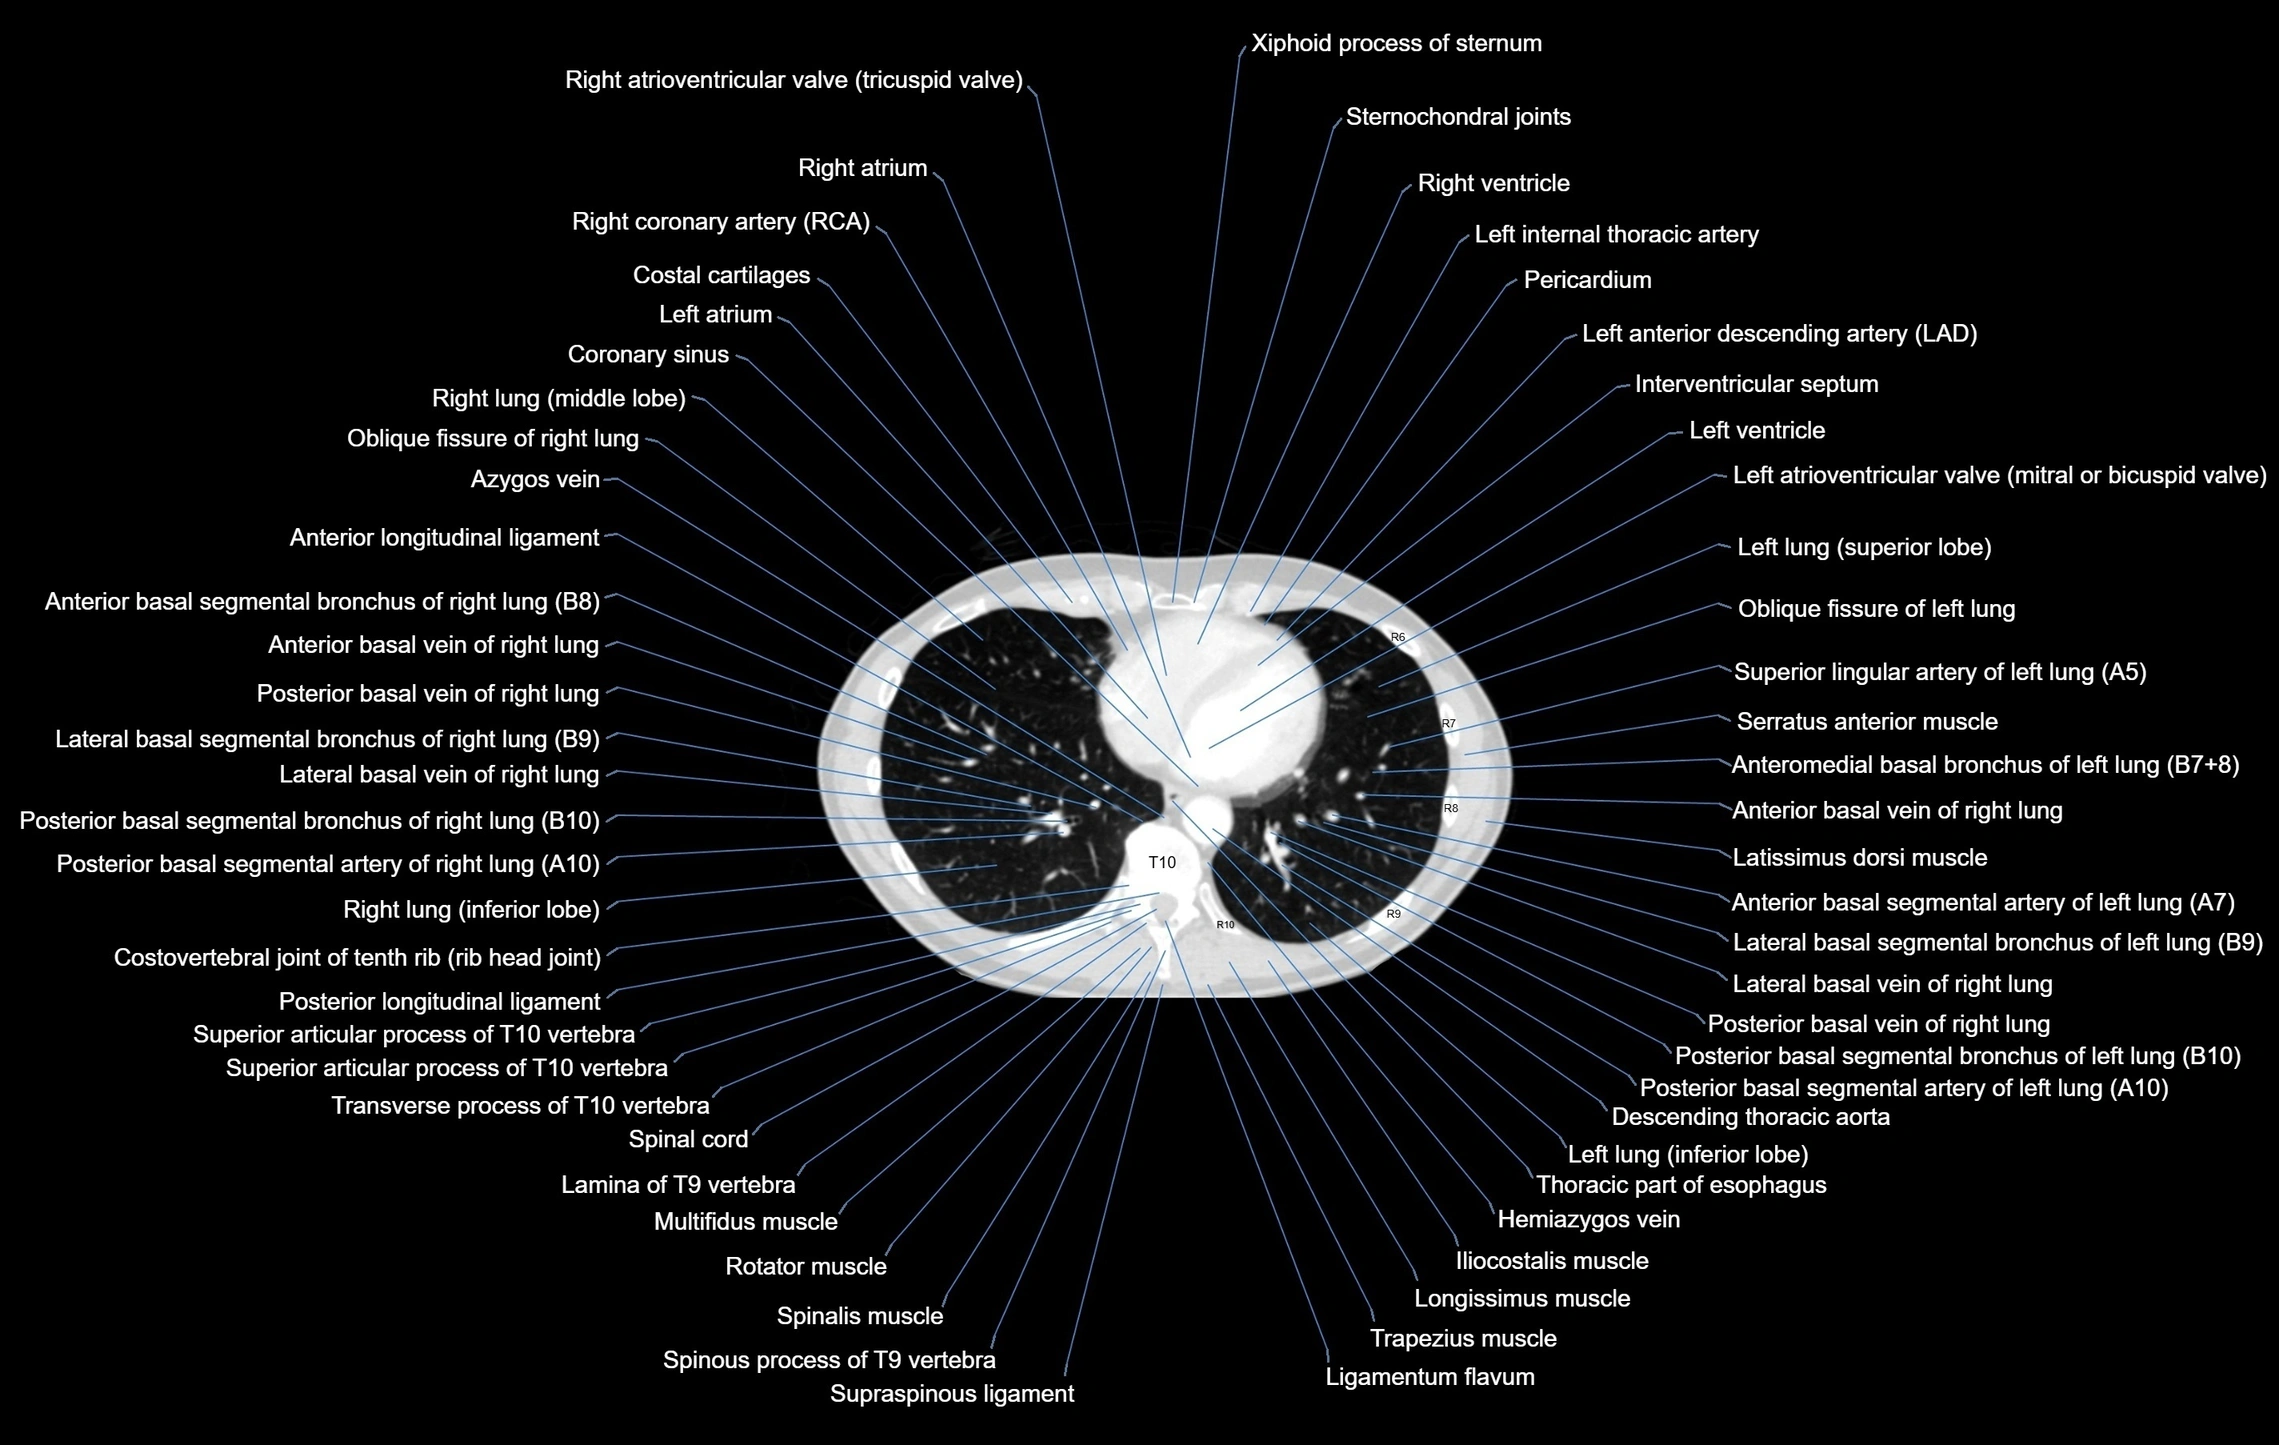

MRI images

CT images